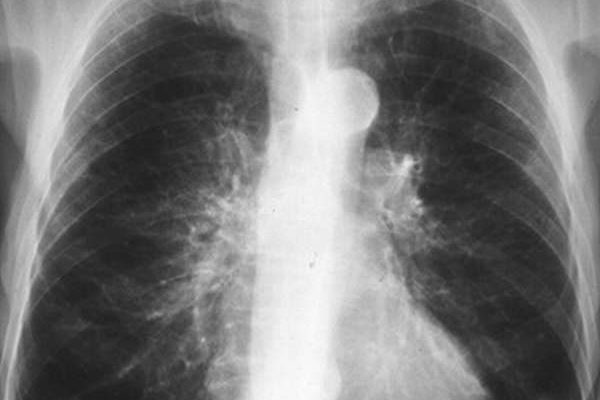

Простой острый бронхит на рентгеновских снимках не виден, визуализируется только обструктивная и хроническая длительная форма заболевания. Давайте рассмотрим примеры того, как выглядит бронхит на рентгеновских снимках:

На фото 1 и 2 показано, как выглядит бронхит на рентгеновских снимках, точнее, каковы симптомы заболевания:

- изменение размеров и структуры корней легких;

- размытость контуров;

- изменение картины легких (обычно усиление);

- Утолщение бронхиальной стенки при хроническом бронхите (симптом «трамвайных рельсов» — фото 3).

Рентген легких при обструктивном бронхите выглядит так:

Для бронхита с обструктивным синдромом характерны:

- повышенная воздухопроницаемость легких;

- низкая диафрагма;

- уплощение диафрагмы и ограничение ее подвижности;

- вертикальное расположение сердца.